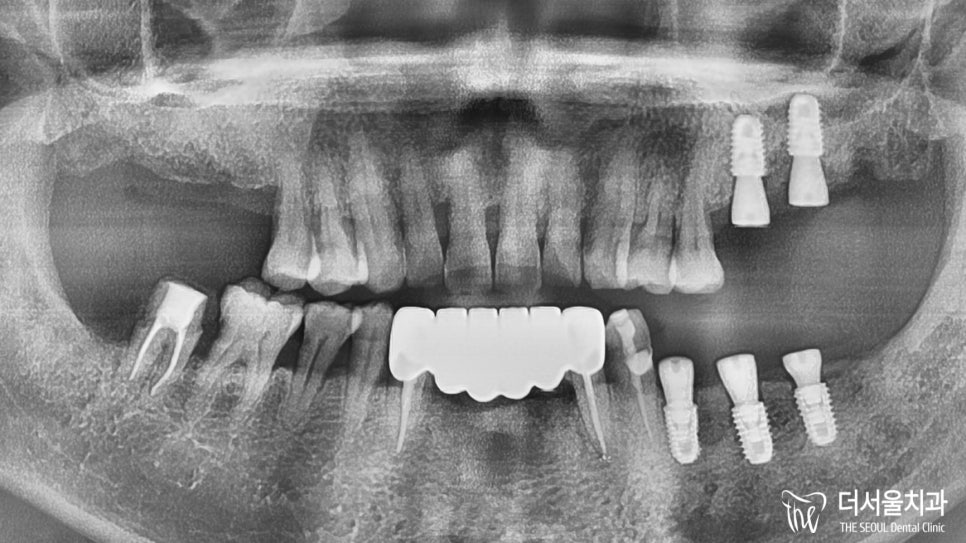

파노라마 사진을 보면 뿌리 끝까지 채워진 모습을 볼 수 있네요.

본격적으로 식립을 하기에 앞서,

골질과 골양, 주변 조직과의 관계를 확인했습니다.

이후 총 5곳에 implant fixture를 심은 다음

잇몸 형성에 도움을 줄 healing abutment까지 체결을 도왔습니다.

연결 이음새 부분이 매끄럽게 잘 이어지고 있는 모습이네요.

식립 후 CT